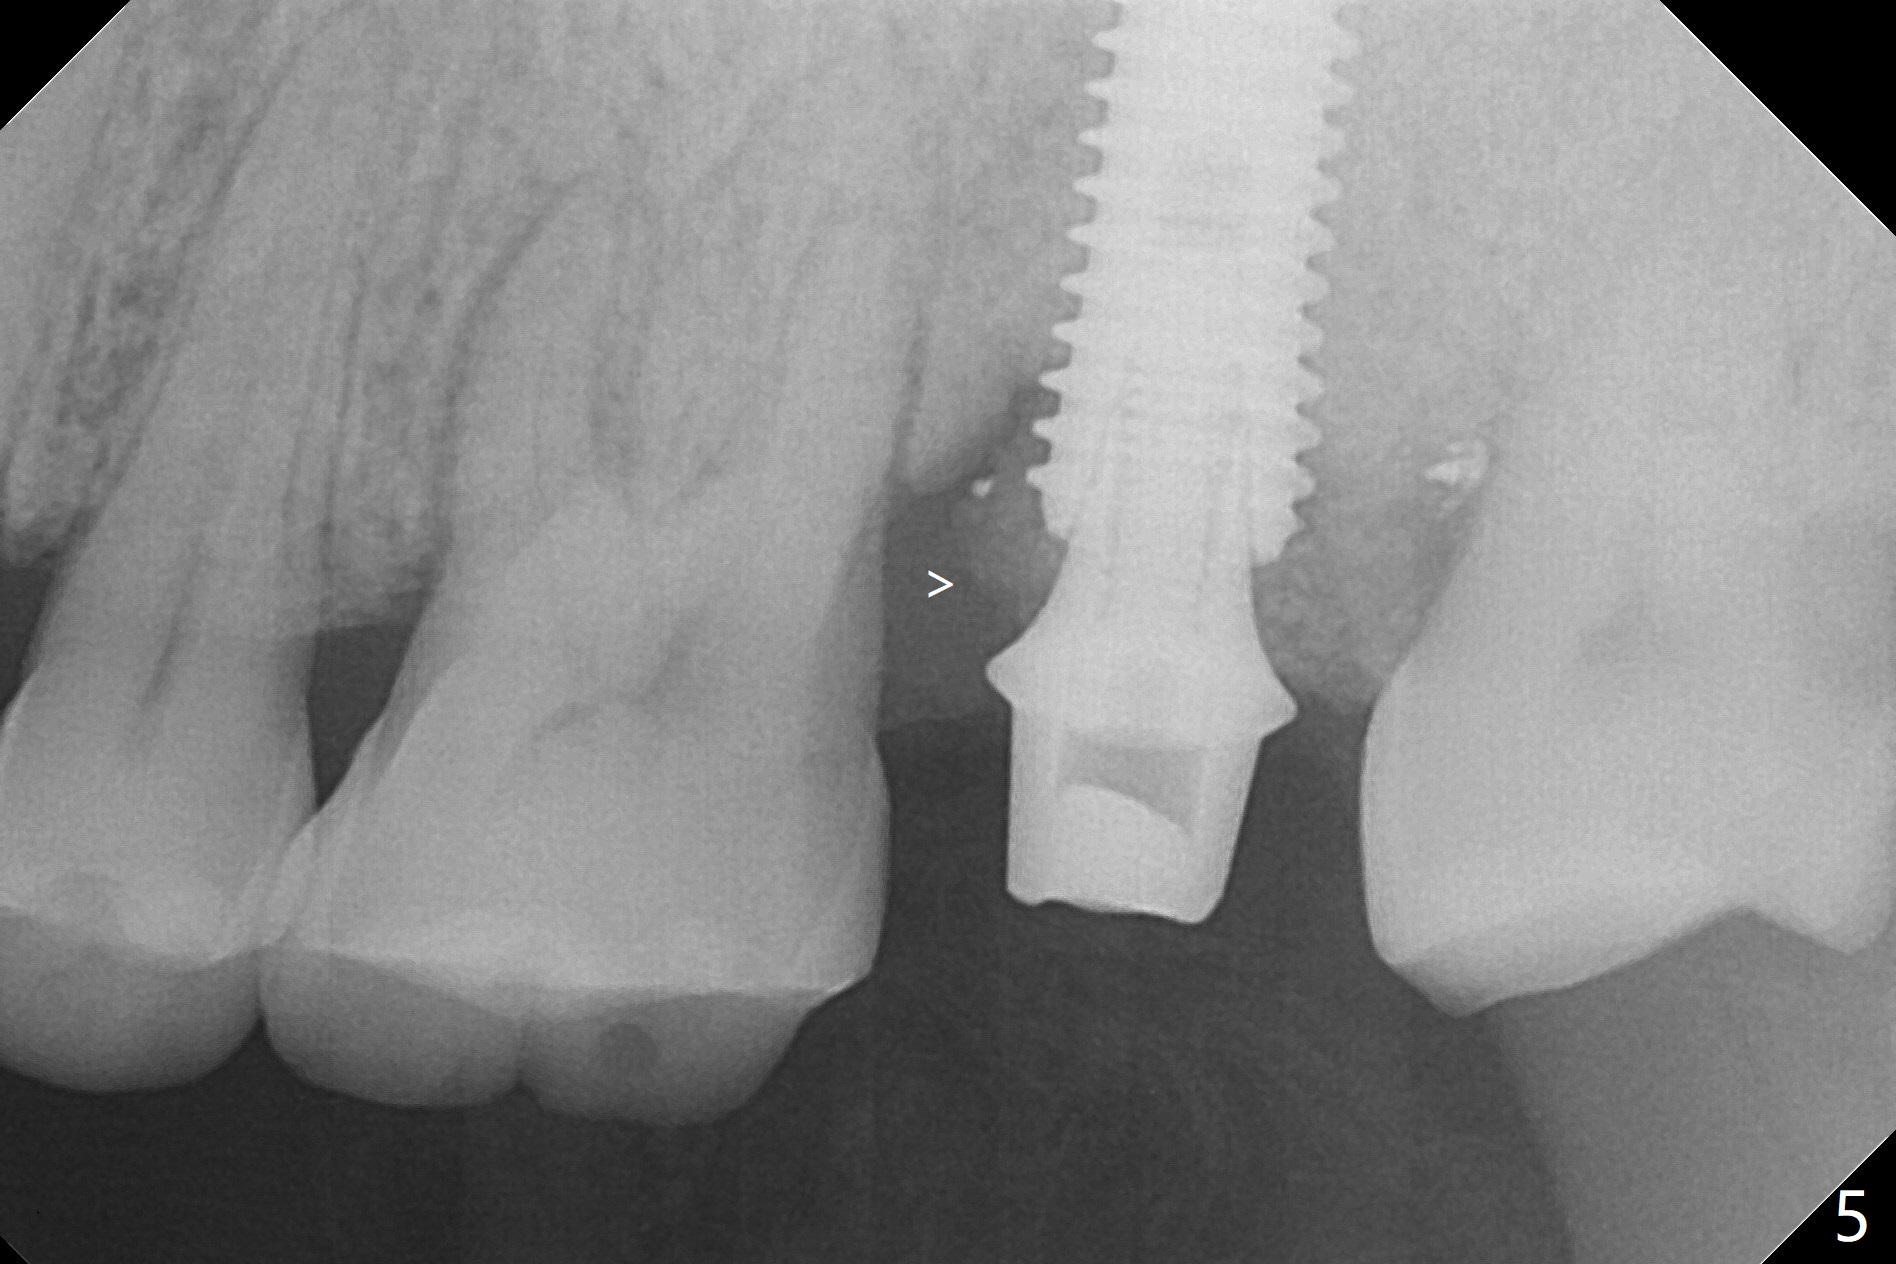

When the patient returns for the tooth #15 extraction and implant, the mesiobuccal residual root has been expelled, while the distobuccal and palatal roots seem to have extruded (Fig.1). The mesial portion of the gingiva (G) is intact and thick. The trajectory of the initial osteotomy is to be changed as shown by red line in Fig.2. The 3.8 mm drill appears to be distal (Fig.3). With mesial bone removal with Lindamann bur, the position of the final implant (5x13 mm) is within normal limit (Fig.4 (50 Ncm)). Because of the thick mesial gingiva (Fig.4 G) and placement of the 5.5x4(2) mm abutment, insertion of mixture of autogenous and Vanilla Graft (*) into the mesial aspect of the implant is difficult (Fig.4 >). Further pushing of the bone graft from the buccal and palatal socket gaps results in more ideal packing (Fig.5 >). If the bone graft were placed first, packing would have been easier. An immediate provisional is fabricated to prevent further mesial shifting of the 3rd molar (Fig.1 arrow). The implant remains stable, while the provisional and abutment are loose 3 months 1 week postop (Fig.6). Impression is taken after abutment cleaning and retightening. Because of the long implant (13 mm), a permanent crown can be cemented early (3 months 20 days postop, Fig.7).